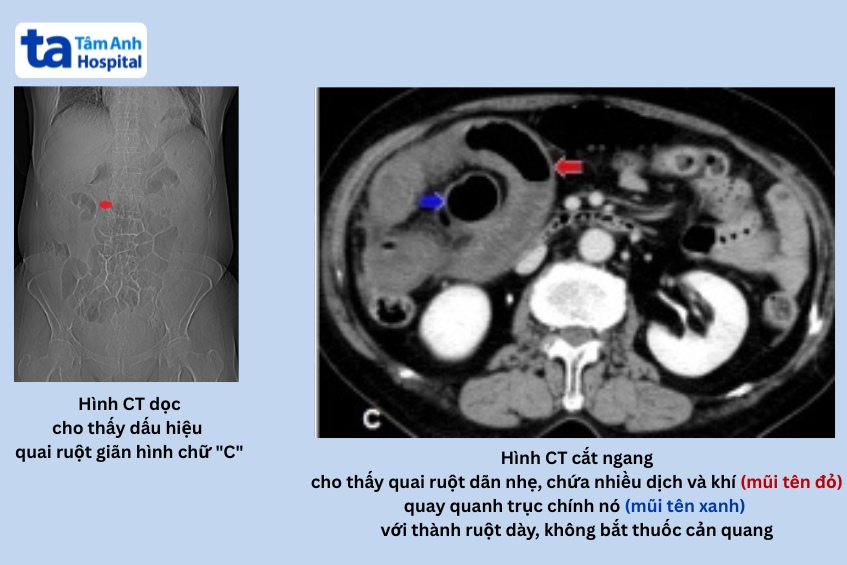

- Chụp cắt lớp vi tính (CT scan) ổ bụng có tiêm thuốc cản quang tĩnh mạch:

- Đây là phương pháp chẩn đoán hình ảnh thường được ưu tiên lựa chọn. CT xác định hai điểm tắc nghẽn liền kề, hình ảnh quai ruột giãn hình chữ “C” hoặc “U” kèm dấu hiệu mỏ chim (beak sign) tại vị trí chuyển tiếp.

- CT cũng phát hiện dấu hiệu xoáy nước (whirl sign) gợi ý xoắn mạc treo, cùng các biểu hiện thiếu máu ruột như phù nề mạc treo, dịch tự do ổ bụng và thành ruột dày không bắt thuốc.

- Hình ảnh chụp CT dựng lại theo mặt phẳng đứng dọc (coronal) và đứng ngang (sagittal) giúp truy vết đường đi quai ruột mà hình cắt ngang có thể bỏ sót.